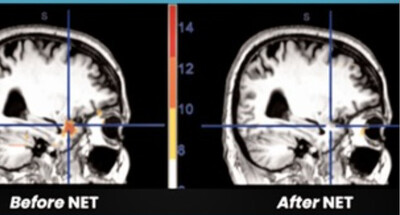

NET - Evidence Based Medicine